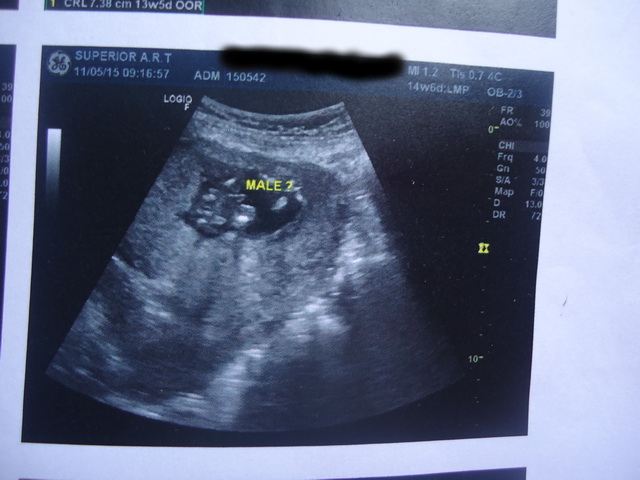

เราไป u/s มา อายุครรภ์ประมาณ 13-14 สัปดาห์ ตามรูปค่ะ

3. ขนาดของน้องเป็นยังไงบ้างคะตามเกณฑ์มั้ย

4. จากภาพเป็น ผช. ชัวร์แล้วใช่มั้ยคะ แอบลุ้นอยากได้ ผญ.